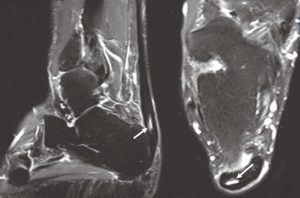

When a tendon or muscle tears, the most specific sign of that tear is a collection of fluid (this feature is true of both MRI and ultrasound imaging). On ultrasound, fluid has no echogenicity, creating an anechoic/very black appearance described above. This is opposite to the standard T2 MRI images that we review to confirm tearing where water is white (Figure 5). There may be variable echogenicity related to tearing due to hematoma formation or hemorrhage, which would often have heterogenous or mixed echotexture.5 The easiest type of tear to identify is a full-thickness tear, as there is complete detachment of the tendon insertion with retraction and fluid filling the gap. If there is no obvious retraction, muscle contraction and movement can be utilized to help demonstrate the extent of tearing. Partial thickness tears can be harder to identify.

Tendon or muscular tearing is present when there is a fluid collection with fiber disruption (Figure 4). Partial tearing is present when a small portion of the tendon has focal fluid within that can be measured. MRI demonstrates a similar finding with a focal fluid collection within the tendon, indicating partial tearing in Figure 5.

Full-thickness Achilles tendon tearing is demonstrated in Figure 6, with more prominent disorganization of fiber orientation and a gap in the continuity of the tendon. There is also pronounced thickening of the Achilles tendon distal to the tear, which indicates that there was tendinosis prior to tearing as tendinosis is a chronic finding and can weaken the tendon. Dynamic imaging is often very useful in determining the integrity of the tendon with active and passive muscle contraction.